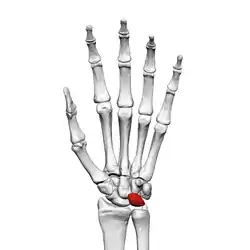

The lunate bone (semilunar bone) is a carpal bone in the human hand. It is distinguished by its deep concavity and crescentic outline. It is situated in the center of the proximal row carpal bones, which lie between the ulna and radius and the hand. The lunate carpal bone is situated between the lateral scaphoid bone and medial triquetral bone.

The lunate is a crescent-shaped carpal bone found within the hand. The lunate is found within the proximal row of carpal bones. Proximally, it abuts the radius. Laterally, it articulates with the scaphoid bone, medially with the triquetral bone, and distally with the capitate bone. The lunate also articulates on its distal and medial surface with the hamate bone.[2]: 708 [3]

The proximal surface of the lunate bone is smooth and convex, articulating with the radius. The lateral surface is flat and narrow, with a crescentic facet for articulation with the scaphoid bone. The medial surface possesses a smooth and quadrilateral facet for articulation with the triquetral bone. The palmar surface is rough, as is the dorsal surface. The dorsal surface is broad and rounded. The distal surface of the bone is deep and concave.[4]